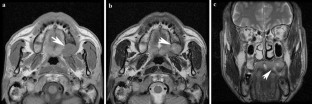

Non-contrast computed tomography and magnetic resonance imaging features of mucoepidermoid carcinoma in the salivary glands

Use of contrast-enhanced cross-sectional imaging is considered standard practice for investigating mucoepidermoid carcinoma (MEC) in the salivary glands. The purpose of this study was to present the common features of MEC on computed tomography (CT) and magnetic resonance imaging (MRI) without contrast enhancements, and to investigate the possibility of discriminating between MEC and pleomorphic adenoma based on the features observed on both modalities.

Twenty cases of biopsy-confirmed MEC originating in the salivary glands were reviewed and characterized by two oral and maxillofacial radiologists with regard to the following aspects: detectability, margin, border, encapsulation, content, contrast between lesion and masticator muscle, and bone changes.

Ninety percent of bone changes caused by MEC were detected by CT and sixty-nine percent of tumor existences were detected by MRI. The lesion border could provide a clue to distinguish MEC from pleomorphic adenoma.

Observation of MEC features was possible by both CT and MRI. Among the features, the lesion border could be a clue to distinguish MEC from pleomorphic adenoma.

Fig. 3